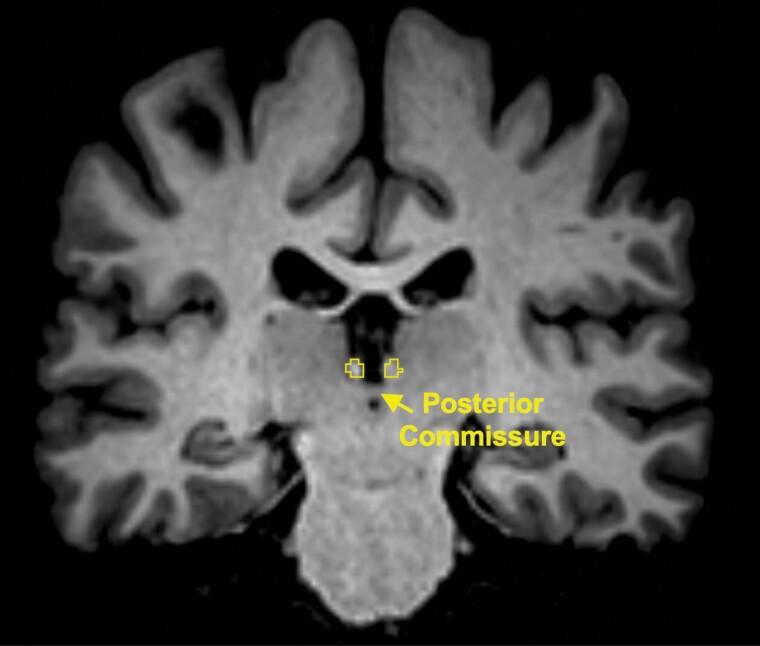

METHODS

Resting-state functional magnetic resonance imaging was conducted in 35 patients with MDD at baseline and 24 hours following treatment with i.v. ketamine. A seed-to-voxel functional connectivity (FC) analysis was performed with the Hb as a seed-of-interest. Pre-post changes in FC and the associations between changes in FC of the Hb and depressive symptom severity were examined.

方法

在基线时和静脉注射氯胺酮治疗后 24 小时对 35 例 MDD 患者进行静息态功能磁共振成像。使用 Hb 作为感兴趣区进行种子到体素功能连接(FC)分析。检查 FC 的前后变化以及 Hb 的 FC 变化与抑郁症状严重程度之间的相关性。